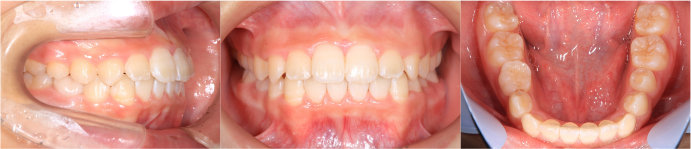

| Case2 |

| 出っ歯 |

| <治療前> |

| <治療後> |

| 主訴 |

上の前歯が出ている |

| 診断名 |

上顎前突 |

| 年齢 |

8歳 |

| 使用装置 |

マルチブラケット装置/ヘッドギア |

| 抜歯部位 |

永久歯の抜歯は無し |

| 治療期間 |

3年6か月 |

| 治療費概算 |

検査・診断料:5万円+税 装置・技術料:25万円+税 来院ごとの処置・管理料:5,000円+税 保定装置料:5万円+税 |

| リスク・副作用 |

特になし |